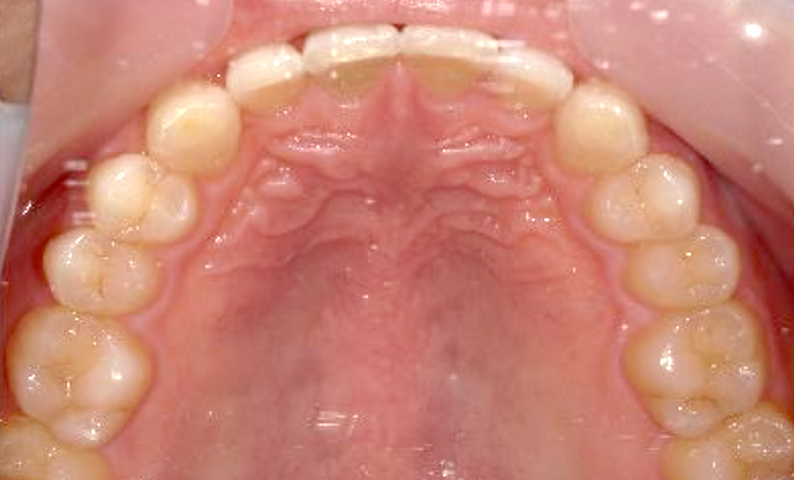

| 治療前 | 治療後 |

|---|---|

|